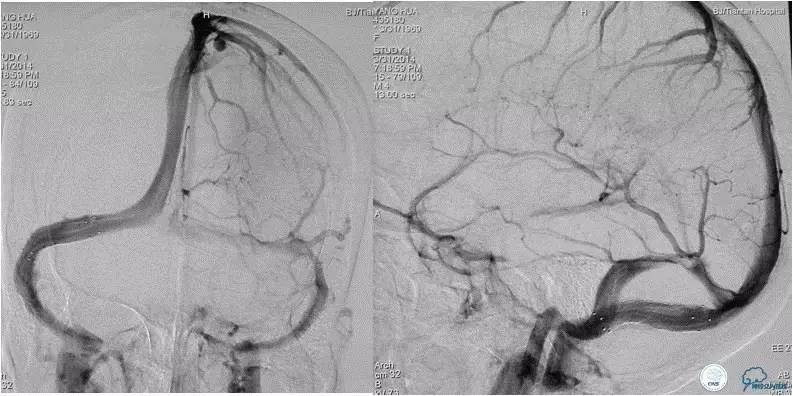

患者入院后,予以行脑动脉造影显示:右侧横窦和乙状窦交界区狭窄,左侧横窦和乙状长段重度狭窄(图3);经股静脉入路行右侧横窦和乙状窦测压显示狭窄两端压力差约为28 mmHg(图4)。遂予以阿司匹林100mg,每日一次,氯吡格雷75mg,每日一次。3d后在全麻插管下行右侧横窦-乙状窦交界处支架植入术。术中采用经右侧颈静脉入路,植入8~30mm 库克公司的ziliver支架,造影见右侧横窦-乙状窦交界处狭窄解除(图5),术中再次测压结果显示狭窄两端压力差约为1mmHg。术后自述双眼视物明显好转,但术后第3天眼底检查双视盘水肿较术前未见明显改善。

随访经过:3月后患者眼底检查双眼视盘水肿明显消退(图6),视力改善:右眼1.0,左眼0.4;8月后患者入院行脑血管造影(DSA)显示右侧横窦-乙状窦交界处支架通畅,未见再狭窄(图7)。

图3:脑动脉造影静脉窦期显示右侧横窦-乙状窦交界区狭窄,左侧横窦显影差,左侧半球血流大部分经右侧静脉窦途径引流。

图5:术中经右颈静脉入路植入8-30mm库克公司ziliver支架,见右横窦-乙状窦交界处狭窄明显解除,术中测压显示狭窄两端压力差约为1mmHg 。